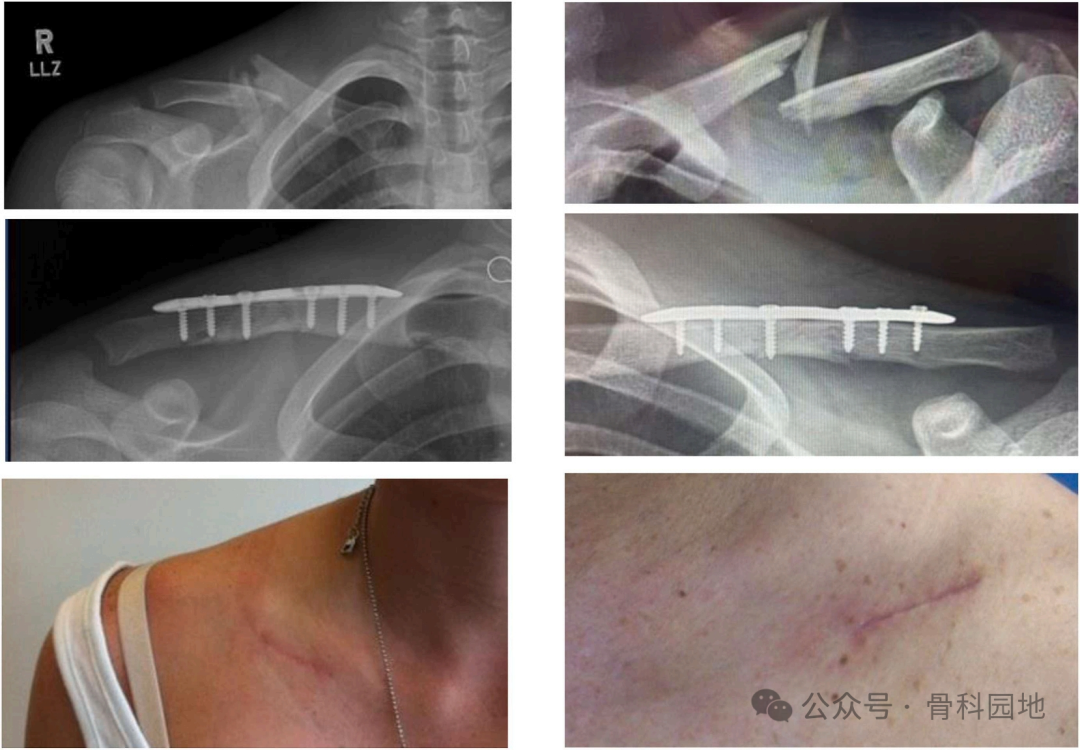

1、锁骨中段粉碎性骨折

4、锁骨骨折的复位和固定,推荐外固定器械辅助固定

6、术后X线片

7、刀口

4、术前X线片,术后8周随访时的X线片,术后瘢痕。